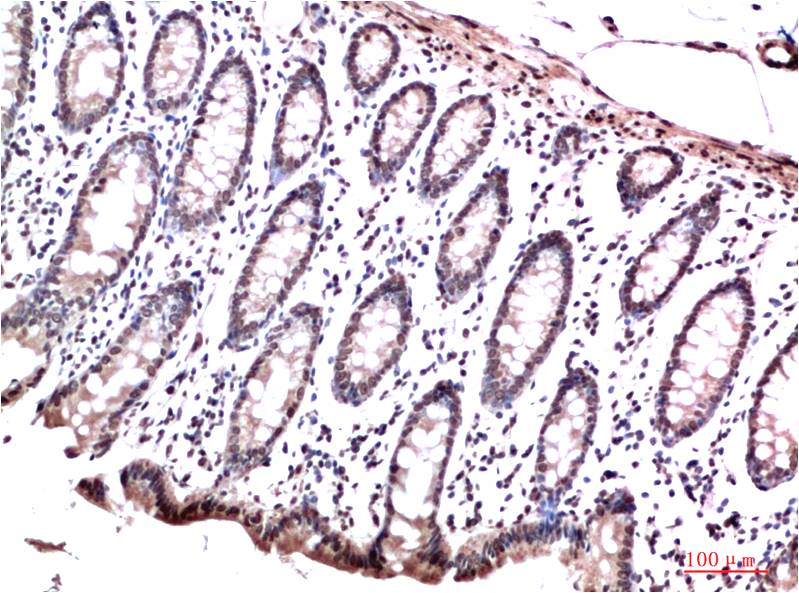

HP-1γ Mouse Monoclonal Antibody(2F5)

Catalog NO.:BE3695

Applications :WB, IHC

Reactivity :H,R,M

Recommended dilutions: WB 1:1,000-2,000 IHC 1:100-200

Specificity: The HP-1γ Mouse Monoclonal Antibody can detects endogenous HP-1γ proteins.